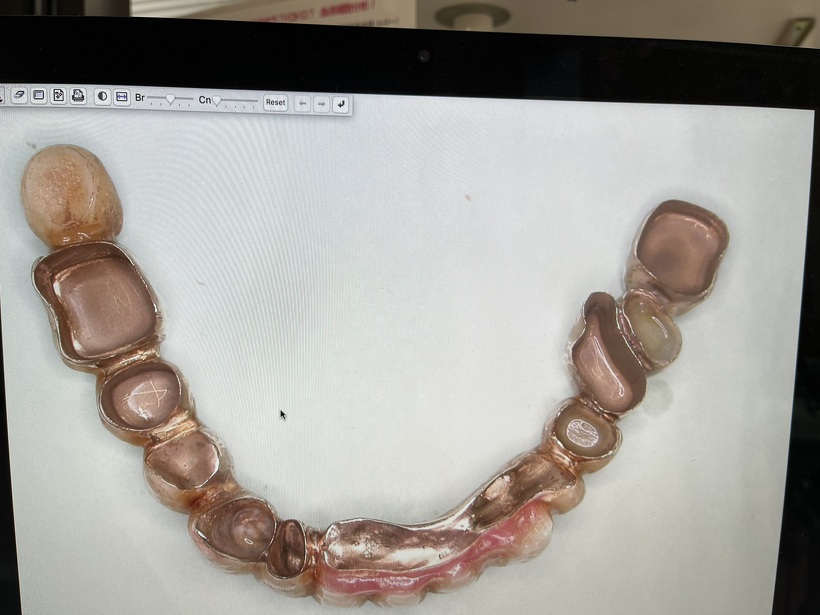

使用中の上総義歯 下コーヌスブリッジ義歯

治療の結果上下で10本が残りました。上顎は2本の歯を総義歯の中に組み込みました。下顎のコーヌスブリッジ義歯 8本の支台歯(実際は7本ですが右下6番は根を2つに分割して使用しています)で14本の歯を作りました。